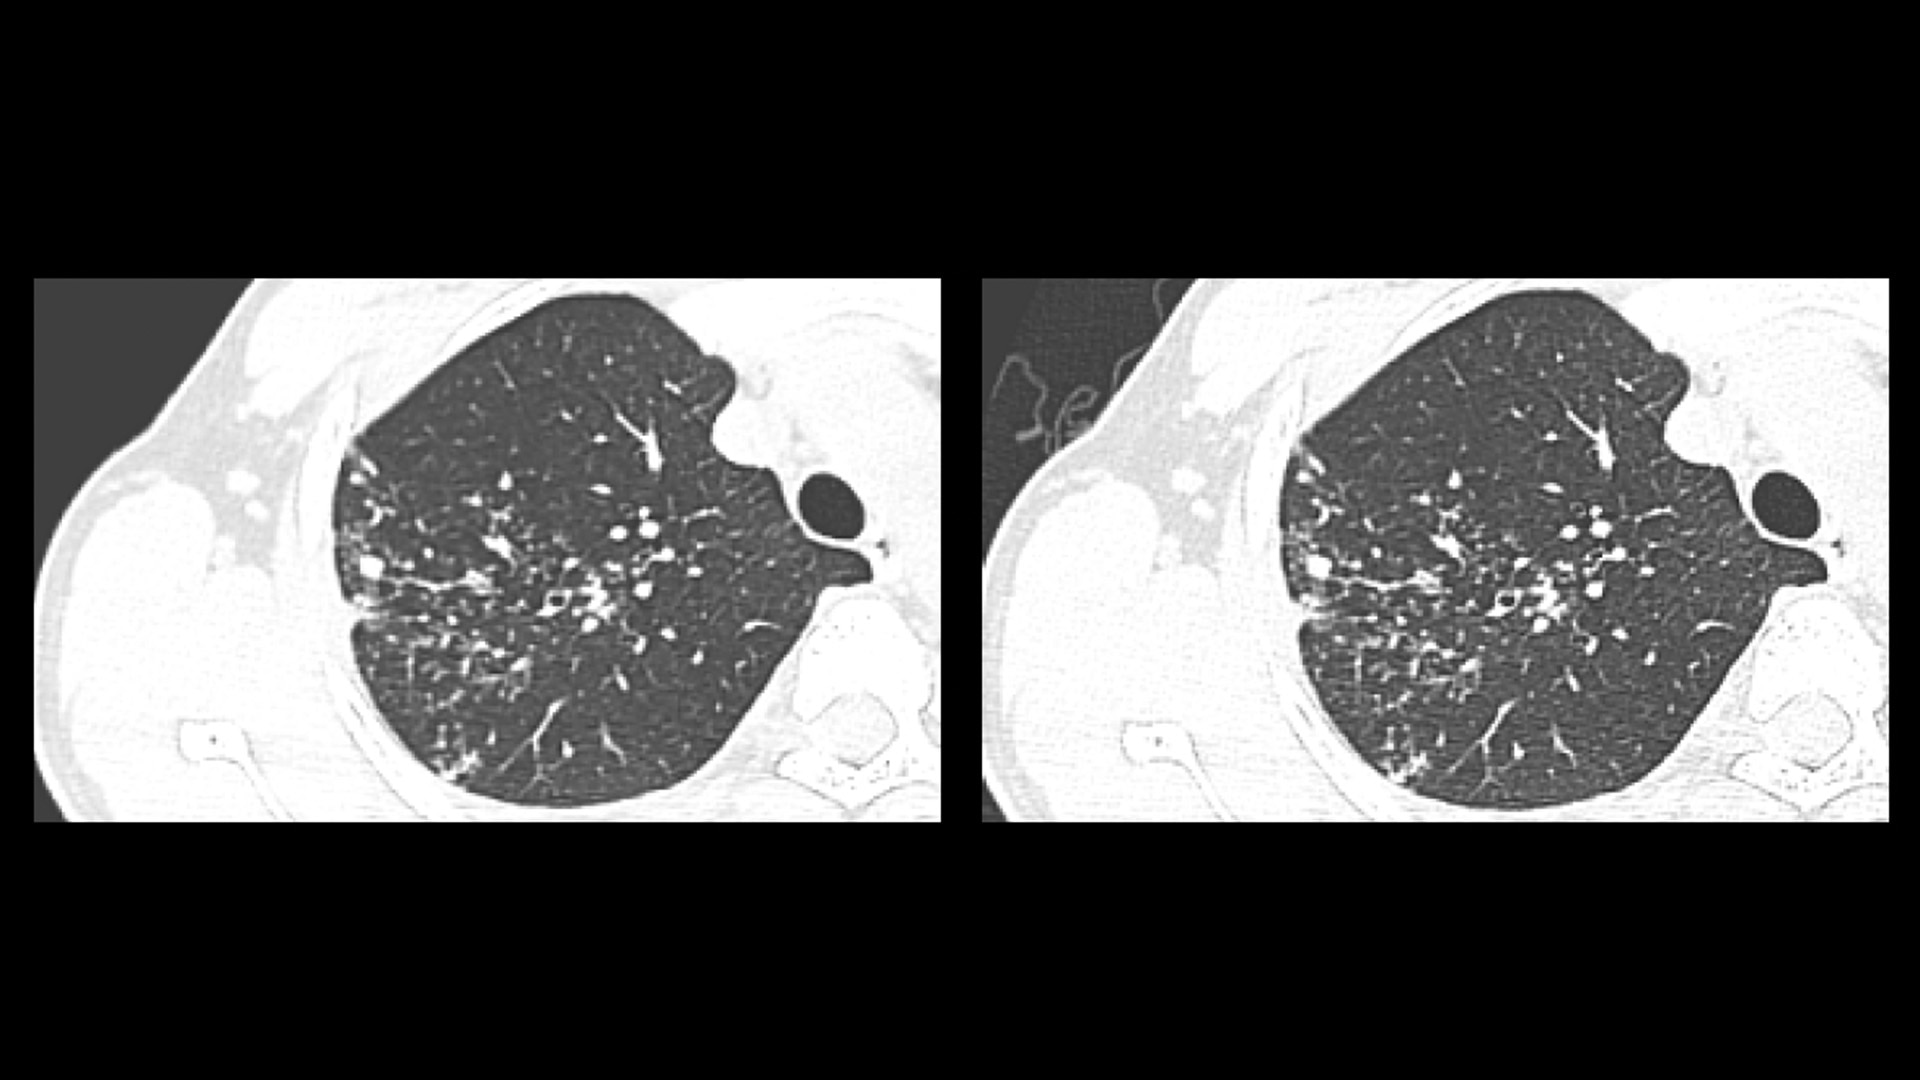

You can also take advantage of speed-enhancing applications like IQ Enhancement (IQE), which can provide faster scans without compromising image quality.

At the heart of Revolution Advance is a high-performance, reliable imaging chain with 42 kW of generator power, a 3.5 MHU X-ray tube and integrated detectors that reduce signal-to-noise by 20%2. This is paired with our smart, dose-reducing reconstruction applications like ASiR2, which can provide up to 40% lower dose while maintaining high image quality2.

When it comes to imaging more challenging cases, such as neuro, oncology or pediatric patients, VISR3. (Volumetric Image Space Reconstruction) reduces noise without impacting image resolution. This means less dose for the patient while maintaining the high-image quality you need for more accurate diagnoses.